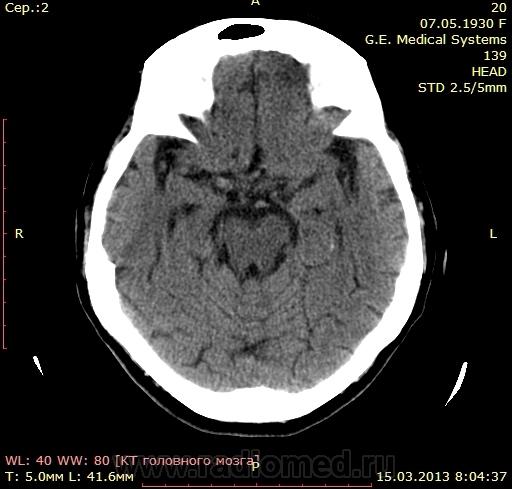

Будьте любезны! Помогите с описанием)) Женщина 1930года рождения поступила в стационар с диагнозом - Повторное ОНМК на фоне атеросклероза и АГ. Сахарный диабет 2 тип.

Попробую, но я не волшебник (тоже только учусь). Слева, перивентрикулярно в бассейне СМА определяются лакунарные инфаркты (или кто поправит- зона пониженной плотности размерами ..х.. мм, плотностью .. ед.Н). Заключение: КТ-признаки подострого ишемического инфаркта в бассейне левой СМА. Правильно?

С лакунарными инфарктами(гиподенсными очагами) может согласен, а что значит гиперденсный очаг в проекции хвостатого ядра?...старый инсульт?..

Как- то не видно лакунарных... Изменения в базальных ядрах слева имеют явно характер дегенеративных, возможно с кальцинозом, расширение переднего рога левого желудочка( относительное!) косвенно это подтвеждает ( по- моему)

Использую термин "зоны патологической плотности". В данном случае, участки повышенной плотности в области базальных ядер левого полушария: головке и теле хвостатого ядра и лентиформном ядре. Более определенно не скажу, судить по джипегу сложновато, дайкомы нужны, но в кровоизлияние не укладывается, передний рог бокового желудочка не компремирован (наоборот, расширен), нет перифокального отека.

По поводу локального снижения плотности белого вещества у передних и задних рогов боковых желудочков - это лейкоареоз. Более правильно лейкоараиоз, но в русскоязычной литературе сложилось как-то так.

а возможно, что  очаги патологической плотности это признакт старого нарушения мозгового кровообращения? В анамнезе у пациентки было ранее ОНМК...

Гиперденсные очаги слева в проекции базальных ядер, что это такое? Кровь? Обызвествление?

Написала бы петехиальное кровоизлияние? базальных ядер слева

- и на КТ-контроль через неделю. Контроль всё и прояснит. Остальные изменения старые и неинтересные.

Это не может быть признаком " старого нарушения". Старое - это всегда понижение плотности, вплоть до плотности ликвора.

"Заключение: КТ-признаки петехиального кровоизлияния базальных ядер слева. КТ- контроль через неделю. Лейкоареоз лобных долей. Гидроцефалия? "